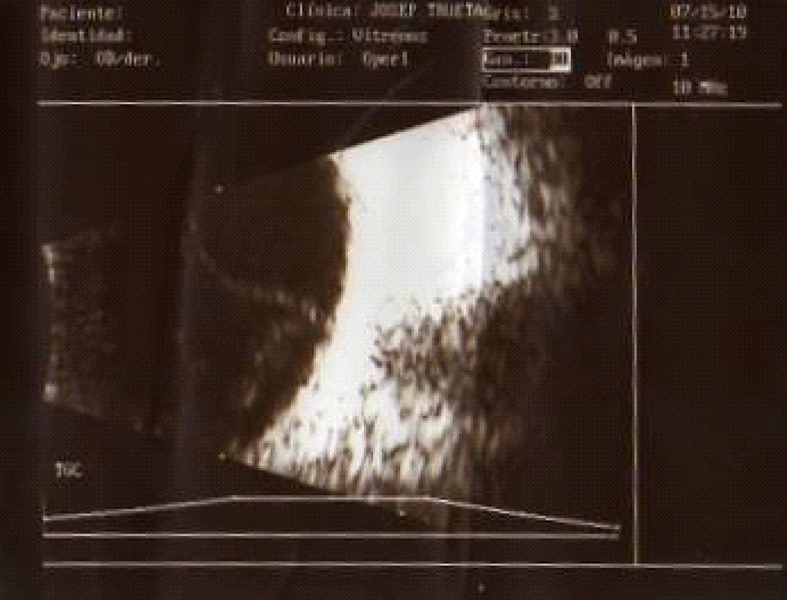

La fase uveítica aguda dura de 2 a 6 semanas y se caracteriza por DR bilateral (Figuras 1, 2 y 3).

Figura 3. Imagen ecográfica del DR seroso.